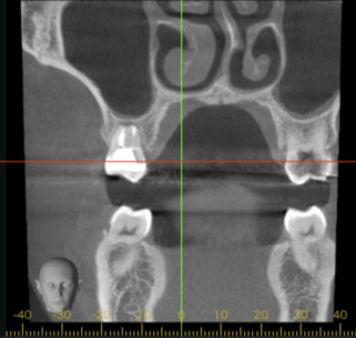

移植12ヶ月後のCT画像①

移植12ヶ月後のCT画像②

移植12ヶ月後。CT画像では、歯根周囲に骨が形成されていることが確認できる。

患者さまは特に違和感なく快適に過ごされているとのこと。